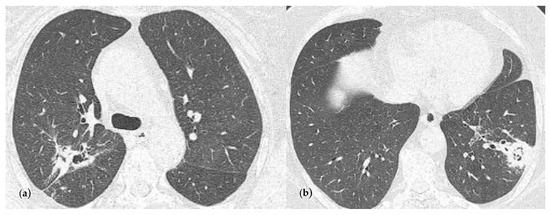

2.2. Blood Workup, Functional Tests, Bronchoscopy, and Radiological Findings